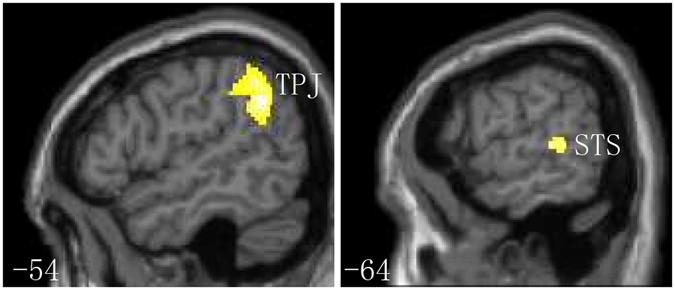

The ability to assess another person's direction of attention is paramount in social communication, many studies have reported a similar pattern between gaze and arrow cues in attention orienting. Neuroimaging research has also demonstrated no qualitative differences in attention to gaze and arrow cues. However, these studies were implemented under simple experiment conditions. Researchers have highlighted the importance of contextual processing (i.e., the semantic congruence between cue and target) in attentional orienting, showing that attentional orienting by social gaze or arrow cues could be modulated through contextual processing. Here, we examine the neural activity of attentional orienting by gaze and arrow cues in response to contextual processing using functional magnetic resonance imaging. The results demonstrated that the influence of neural activity through contextual processing to attentional orienting occurred under invalid conditions (when the cue and target were incongruent versus congruent) in the ventral frontoparietal network, although we did not identify any differences in the neural substrates of attentional orienting in contextual processing between gaze and arrow cues. These results support behavioural data of attentional orienting modulated by contextual processing based on the neurocognitive architecture.

评估他人注意力方向的能力在社交交流中至关重要,许多研究报告了注视和箭头线索在注意力引导方面的相似模式。神经影像学研究还表明,注视和箭头线索对注意力的影响没有质的区别。然而,这些研究是在简单的实验条件下进行的。研究人员强调了上下文处理(即线索和目标之间的语义一致性)在注意力引导中的重要性,表明社会注视或箭头线索的注意力引导可以通过上下文处理来调节。在这里,我们使用功能磁共振成像研究来检查注视和箭头线索对注意力引导的神经活动对上下文处理的反应。结果表明,在腹侧额顶网络中,通过上下文处理对注意力引导的神经活动的影响发生在无效条件下(当线索和目标不一致时),尽管我们没有发现注视和箭头线索在上下文处理中的注意力引导的神经基质有任何差异。这些结果支持基于神经认知结构的基于行为数据的注意力引导受上下文处理调节的观点。